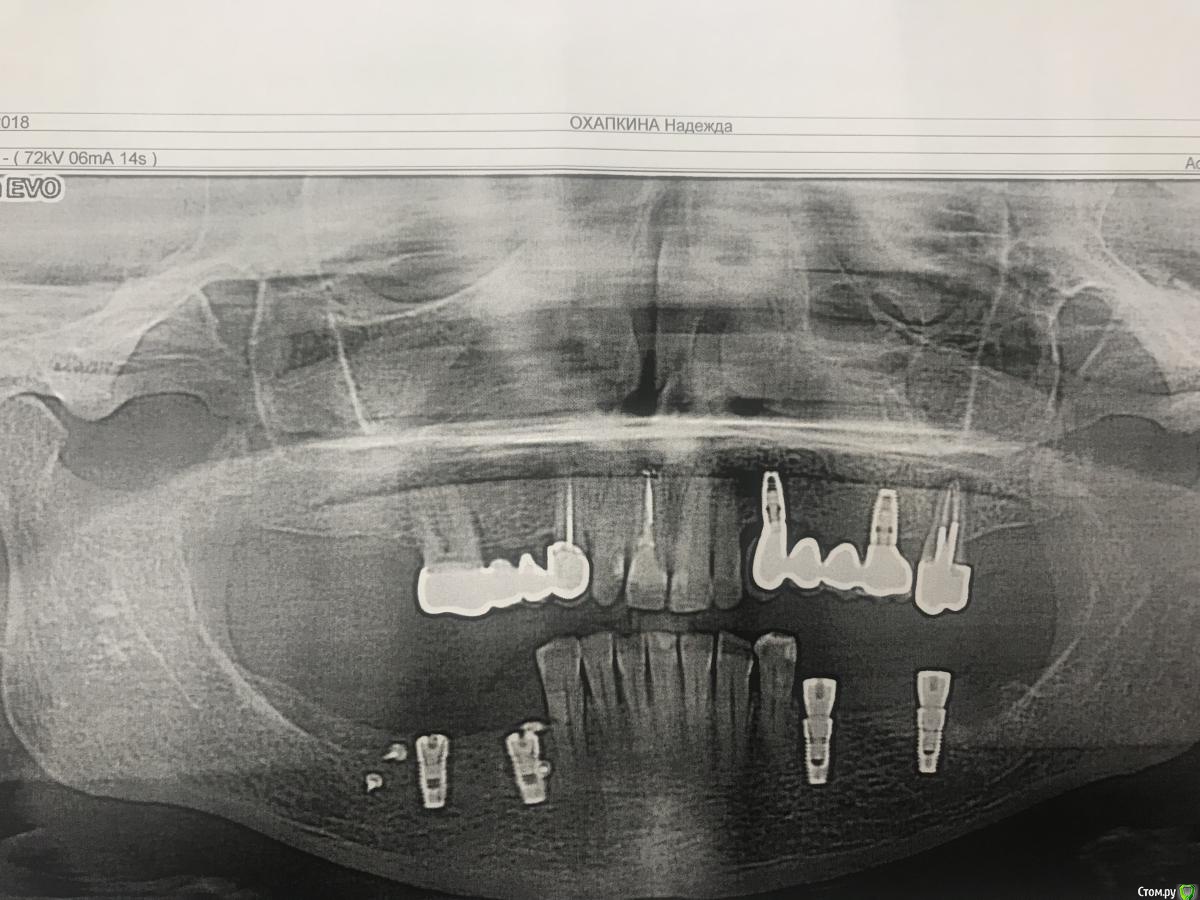

Santi Опубликовано 19 сентября, 2018 Автор Поделиться Опубликовано 19 сентября, 2018 Кт до 34, 3644,46 Ссылка на комментарий